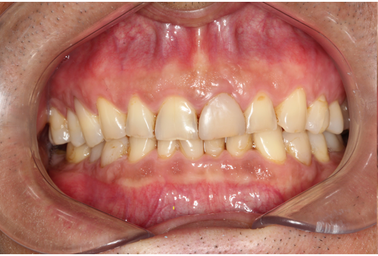

Mr NK, a 52-year-old male, presented with concerns of gradually shortening teeth and sensitivity to cold drinks. He also reported feeling self-conscious about his smile in photos. He is medically fit and has been using a night guard for his sleep-related grinding habit for the past year. Clinical examination revealed moderately worn dentition from erosion and attrition, along with mild crowding of the lower anterior incisors.

Intra-Oral Pictures (Before)